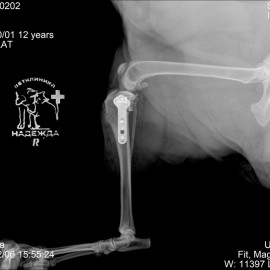

Пациент собака по кличке Линда возрастом 12 лет из города Вельск Архангельской области. Хозяин обратился с жалобой на хромоту на правую заднюю лапу. Проведены исследования, в ходе которых был поставлен диагноз: разрыв передней крестообразной связки правого коленного сустава. Проведена операция - TPLO.

Снимок 1 до операции.